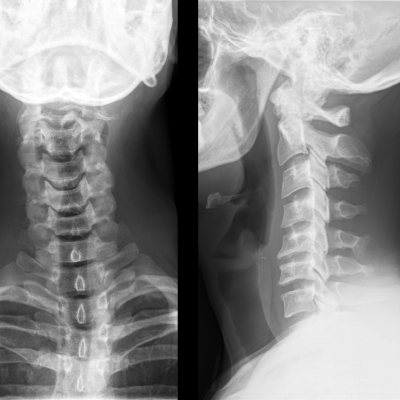

En la disertación el Dr. Zapata presentó el caso de un deportista profesional, jugador defensa central de un equipo de fútbol, que sufrió una hernia de disco cervical y fue tratada en el Hospital FM Habana con prótesis de disco.

La artroplastia de disco cervical puede ser una opción de tratamiento satisfactoria para deportistas con discopatía cervical, permitiendo una vuelta precoz y sin secuelas a la práctica deportiva, ya que es una técnica sin limitación de la movilidad.

Este tipo de cirugía permite la realización precoz de ejercicios y actividades, y no precisa de collarín postoperatorio.

En las conclusiones del caso, compartió los resultados con una recuperación completa en unas semanas, así como la rápida incorporación al equipo, manteniéndose activo y titular como defensa central. Tres años después continúa al mismo nivel sin complicaciones, confirmando el éxito del tratamiento.